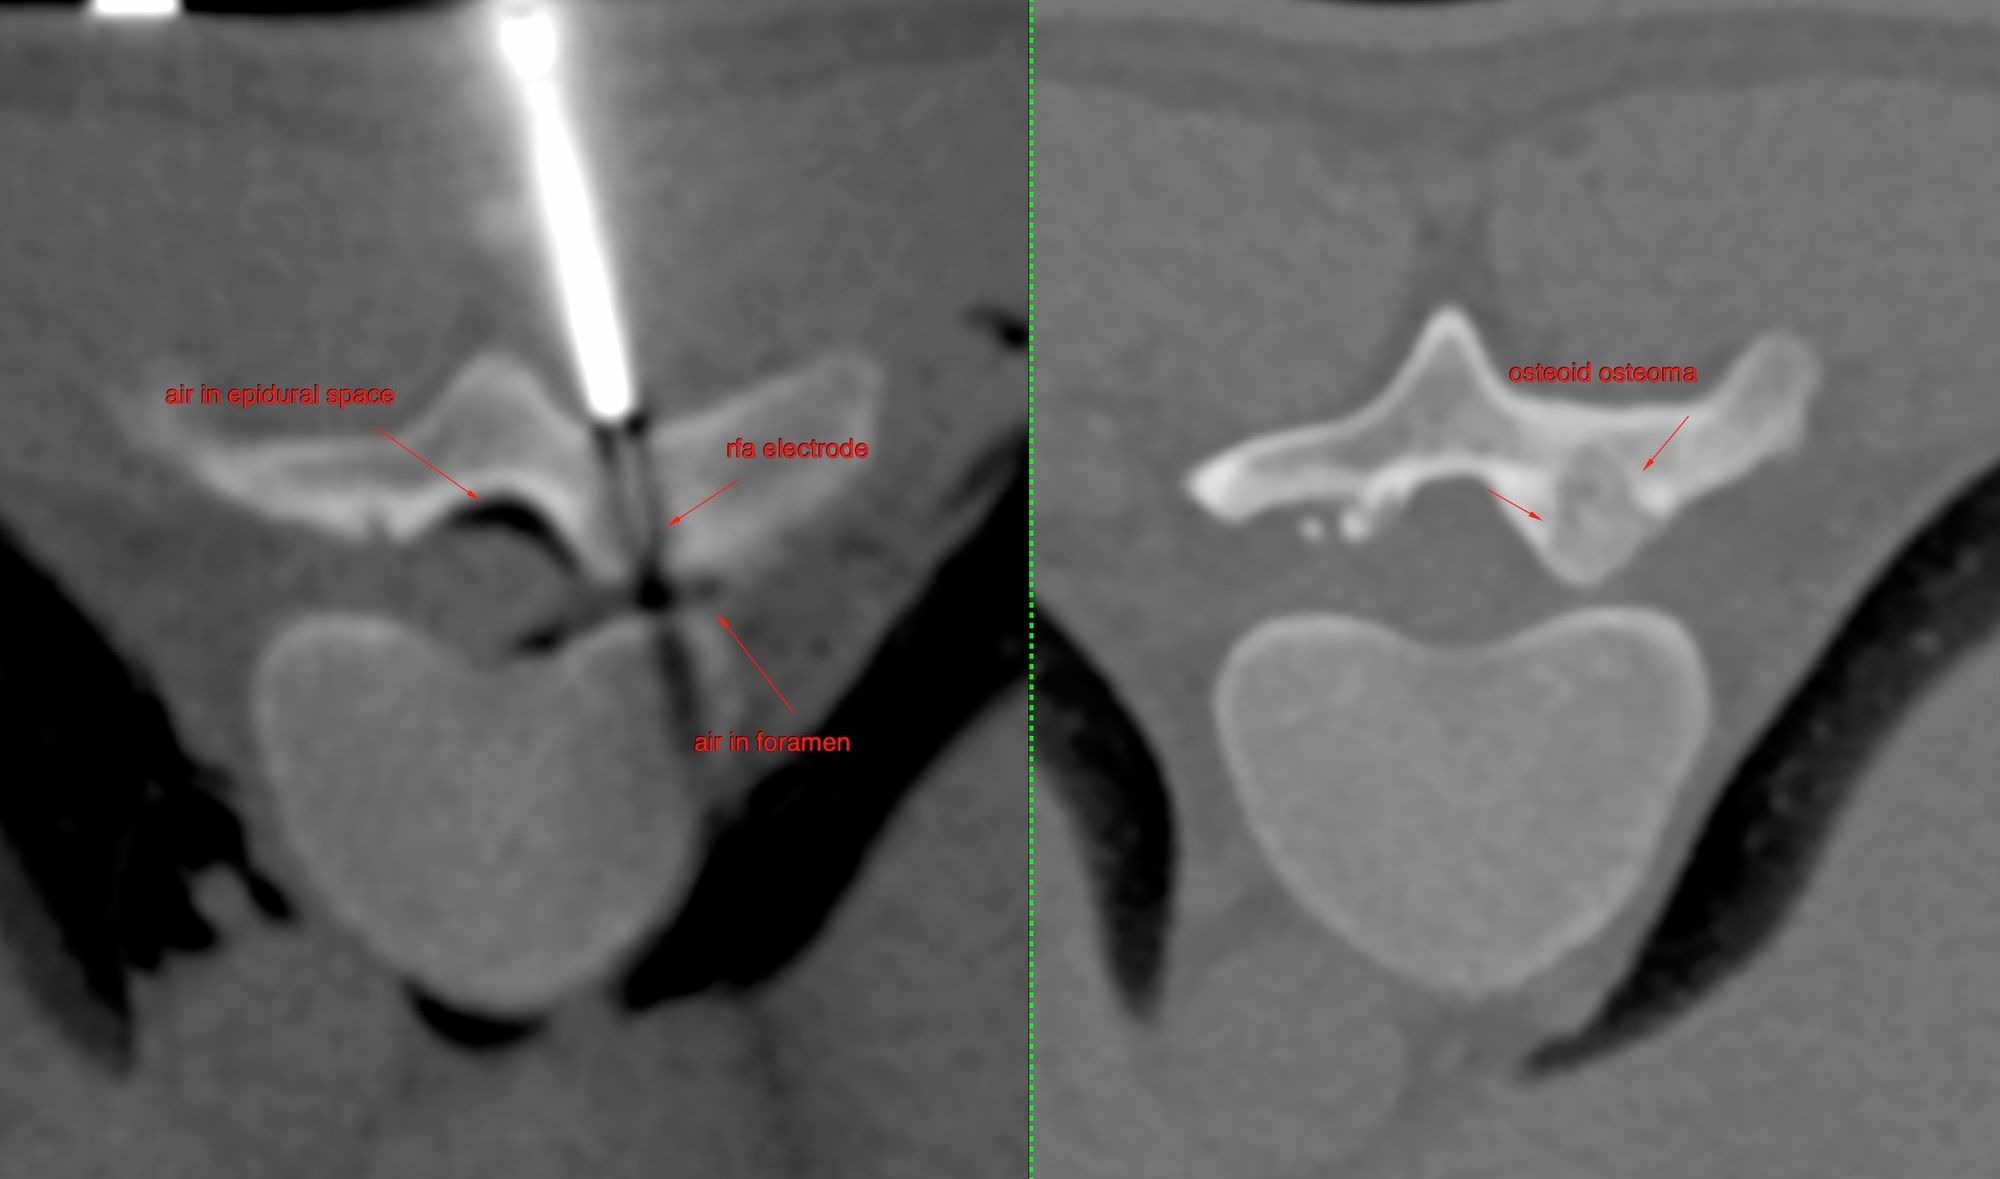

Case 40: Radiofrequency Ablation (RFA) of D10 Pars Osteoid Osteoma